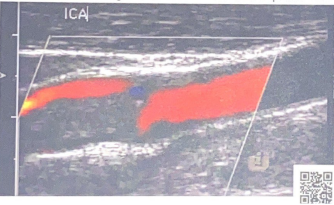

Patient is 38 y/o female with stroke like symptoms. No risk factors or medical history. You take this image of distal ICA.

1. What is the sonographic description of distal ICA?

2. What does this indicate or what is possible diagnosis?

3. Is this related to atherosclerosis?

4. What is important in patient clinical presentation for possible diagnosis?

5. Which other vessels most likely impacted by this?

string of pearls

FMD

No (congenital abnormality)

young female

Renal artery’s